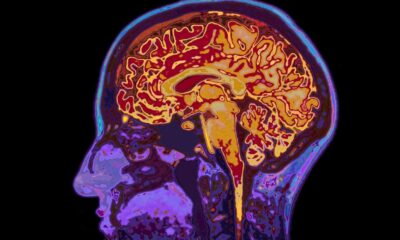

New Study Reveals Brain Development Stages Up to Age 32

Recent research conducted by the University of Cambridge has unveiled significant insights into the timeline of human brain development. The study identifies five key epochs in brain maturation, suggesting that the brain remains in a state of adolescence until approximately 32 years of age. Additionally, the research indicates that signs of ageing begin to manifest around 66 years.

The findings illustrate a comprehensive framework of cognitive development that includes four major turning points throughout a person’s life. These critical stages highlight not only the evolution of cognitive capabilities but also the implications for psychological well-being at various ages.